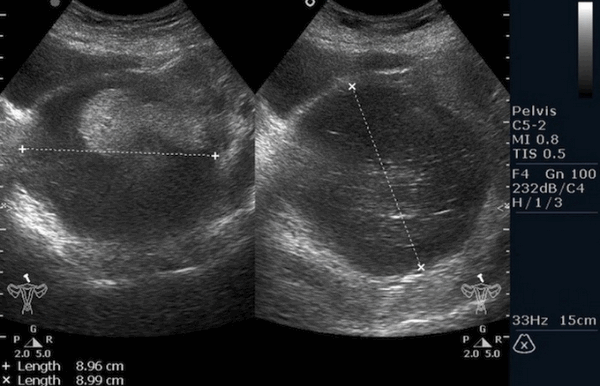

Ультразвуковое исследование (УЗИ) мошонки является предпочтительным начальным визуализирующим исследованием для оценки образования яичка. УЗИ может подтвердить наличие новообразования, определить его расположение и оценить состояние противоположного яичка (рис. 4). Чувствительность метода достаточно высокая - от 92 % до 98 %.

Снимок УЗИ яичка